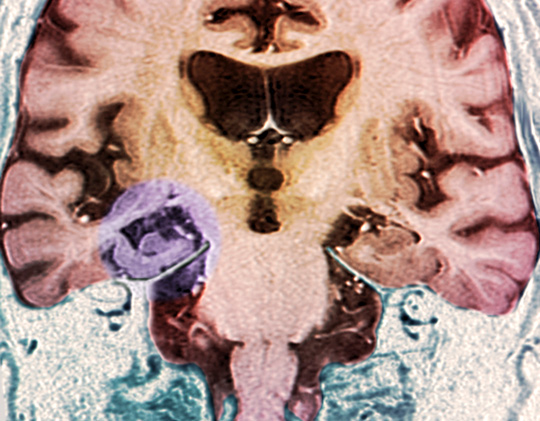

Farget MR-skann av koronal seksjon av hjerne og hjernestamme (nederst til venstre) hos en pasient med Alzheimers sykdom viser plakk i høyre hippocampus. Illustrasjon: Science Photo Library